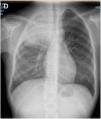

Presentamos a una paciente de 11 años, previamente sana, que presenta masa interescapular, omalgia derecha y síndrome constitucional de 6 meses de evolución1. Se realiza estudio analítico donde destaca leucocitosis con desviación izquierda, elevación de VSG y LDH. El estudio radiológico confirma lesión pulmonar seudotumoral y extensión extrapulmonar con condensación neumónica (figura 1, imagen Rx) (figura 2, imagen TC).

TC torácica. Condensación alveolar pulmonar en segmentos apical y posterior del lóbulo superior derecho, con broncograma central y hepatización periférica. Moderado aumento de tamaño de ganglios en localización paratraqueal derecha, en hilio pulmonar derecho y área subcarinal. Aumento difuso de componente de partes blandas, sin límites precisos, afectando a la pared apical y posterior de hemitórax derecho, interdigitándose a través de espacios intercostales y afectando musculatura paraespinal derecha.